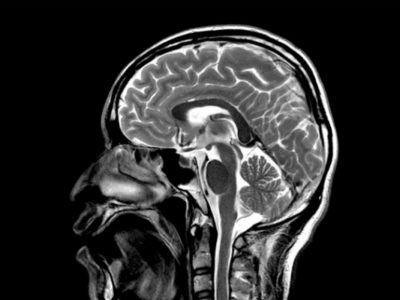

10 фактов о МРТ Один из главных инструментов в нейронауках — магнитно-резонансный томограф. Мы предлагаем подборку из десяти интересных или Без рубрики Окт 10 0